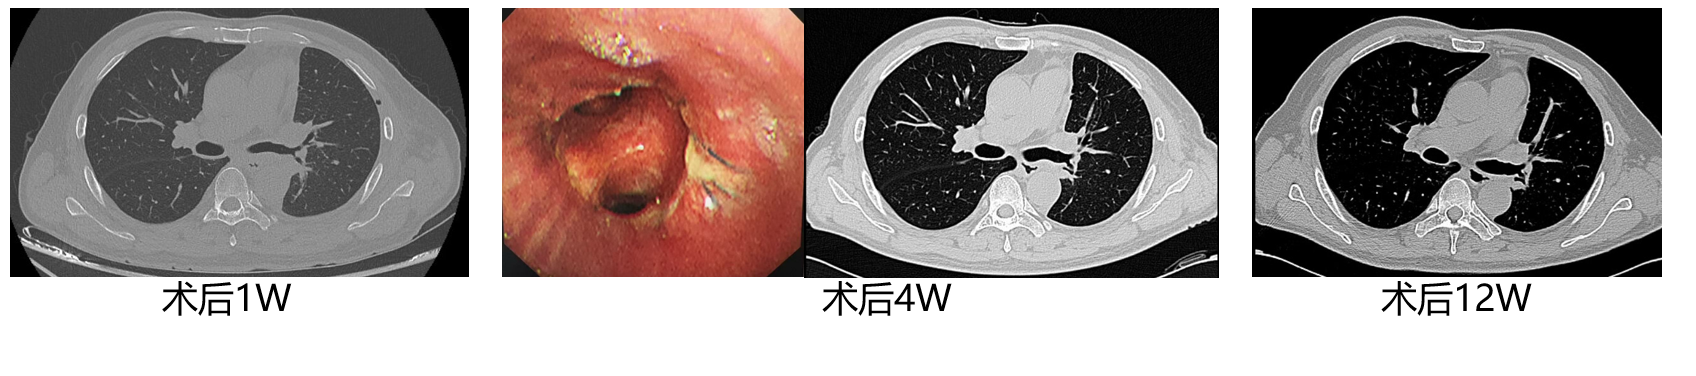

影像学:原发肿瘤最大径从3.7cm缩小至1.5cm;阻塞性肺炎吸收;PET-CT示SUVmax从26.9降至3.6。

4.png

支气管镜:左下肺开口新生物较前明显退缩。

5.png

疗效评价:部分缓解(PR,肿瘤缩小32%)。